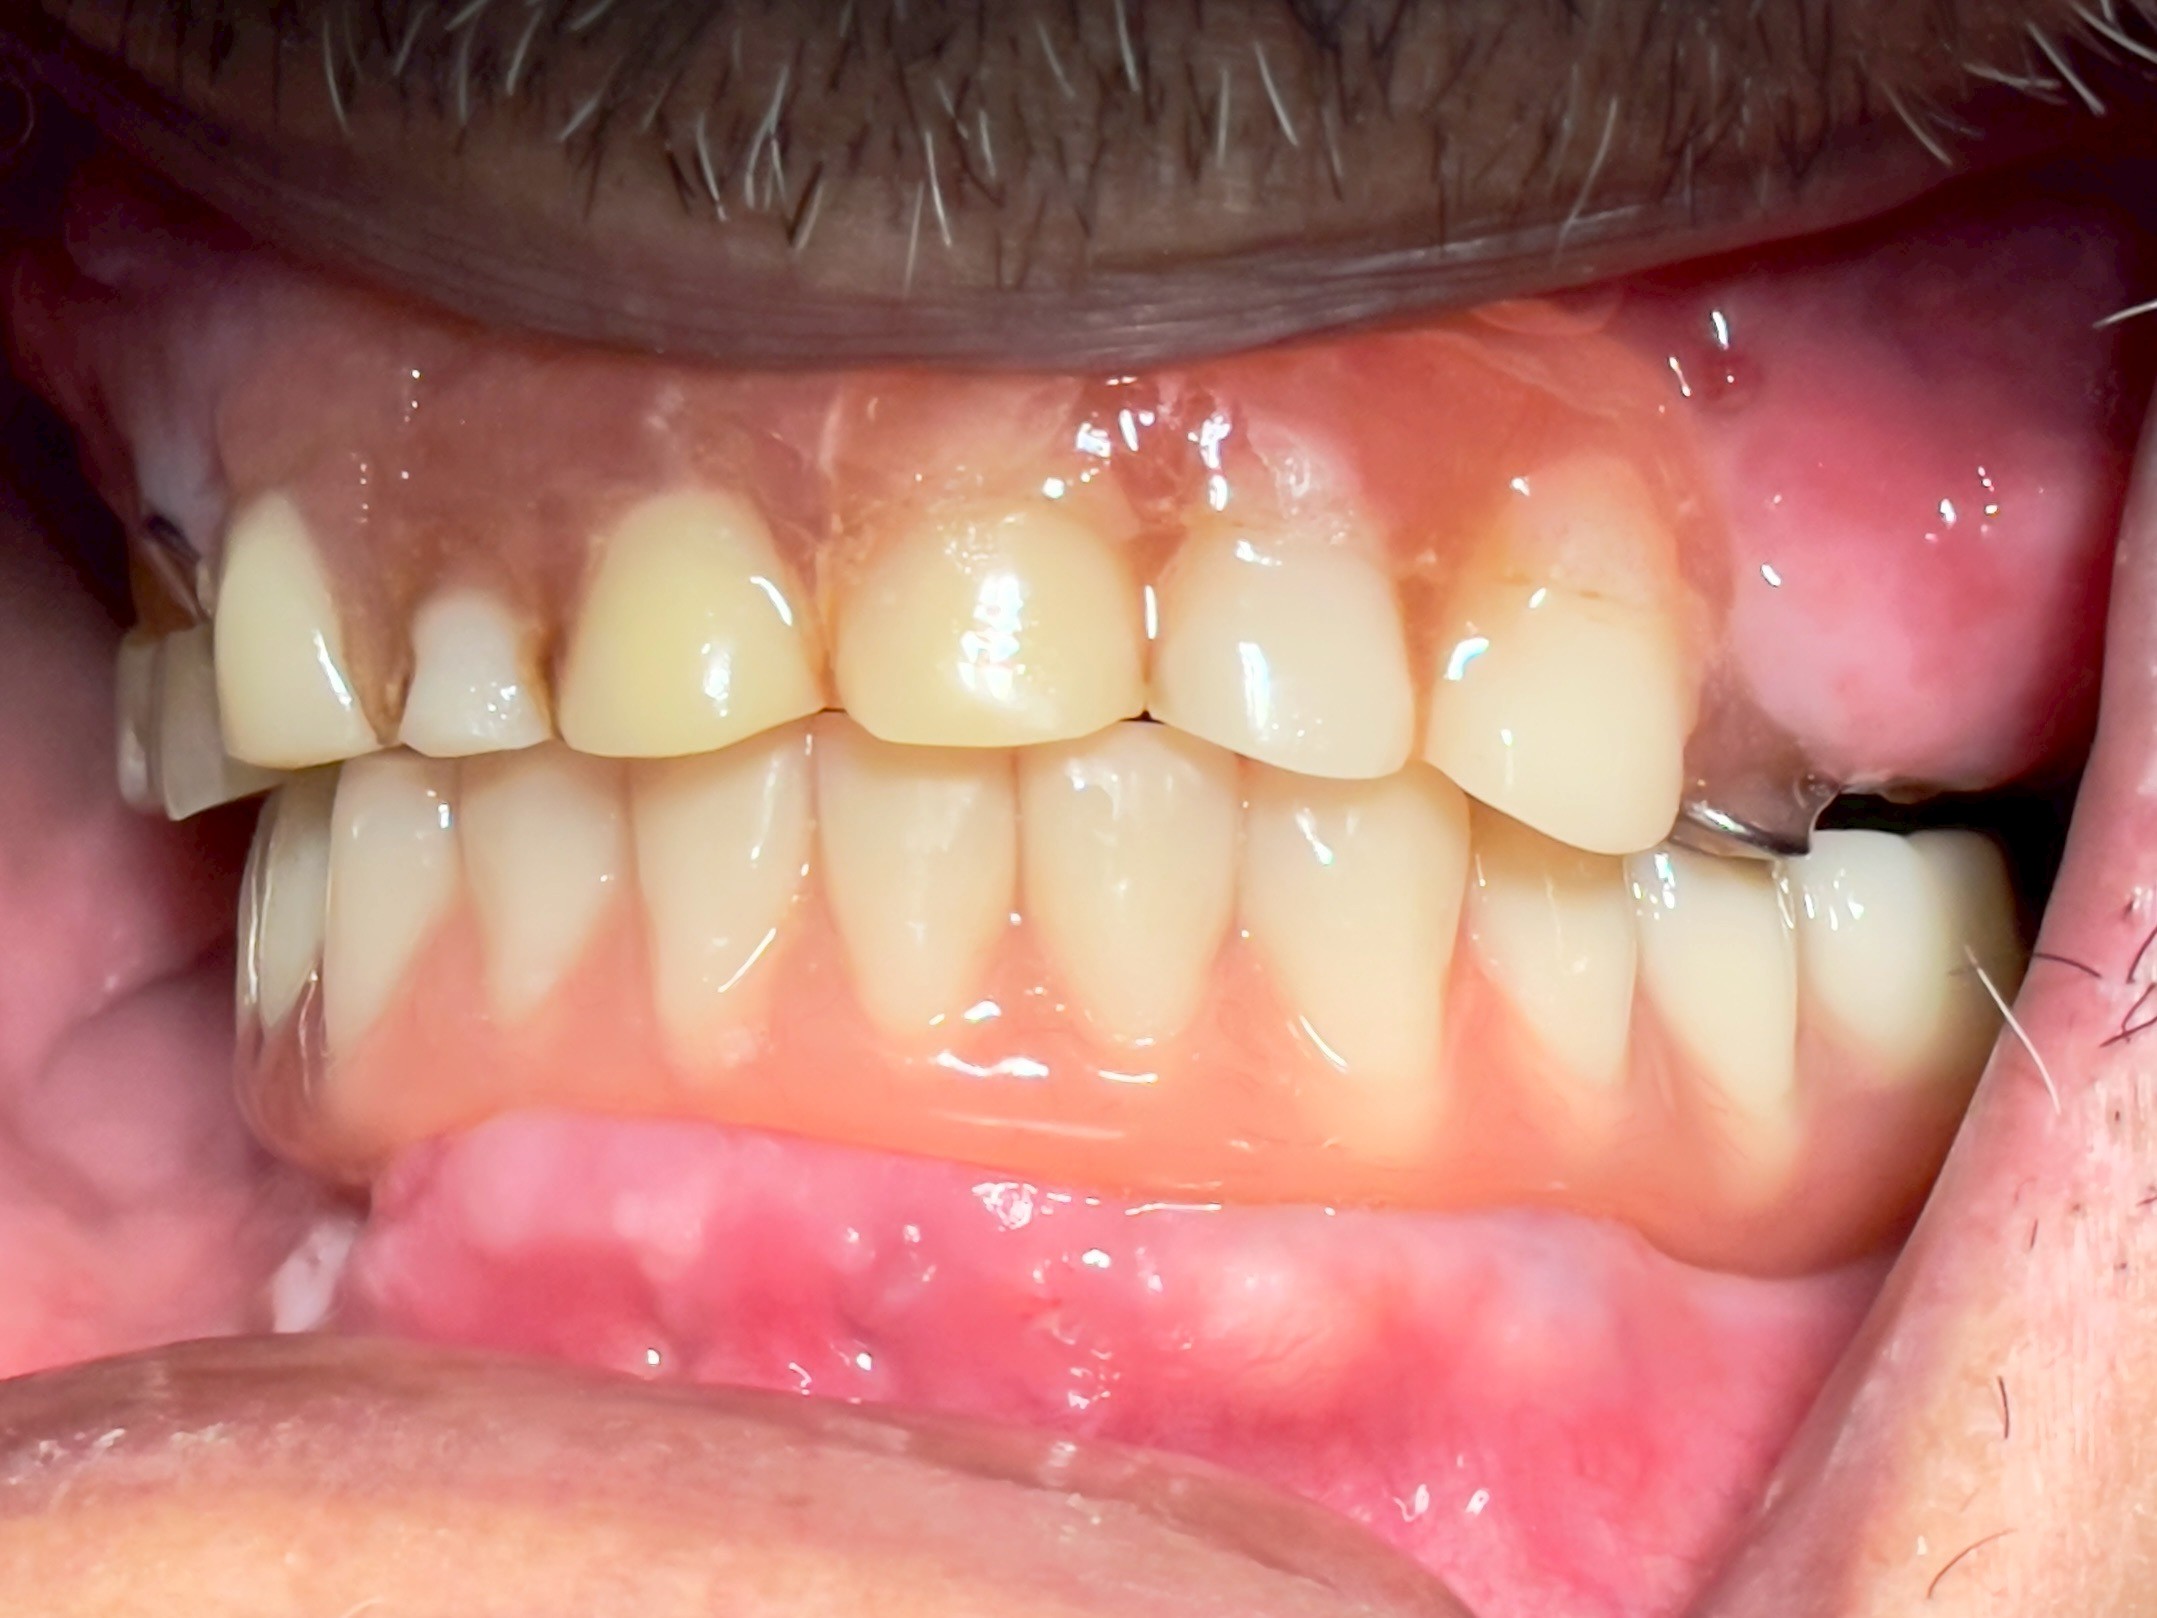

All-on-4 Implants Lower Jaw + Partial Denture Upper Jaw